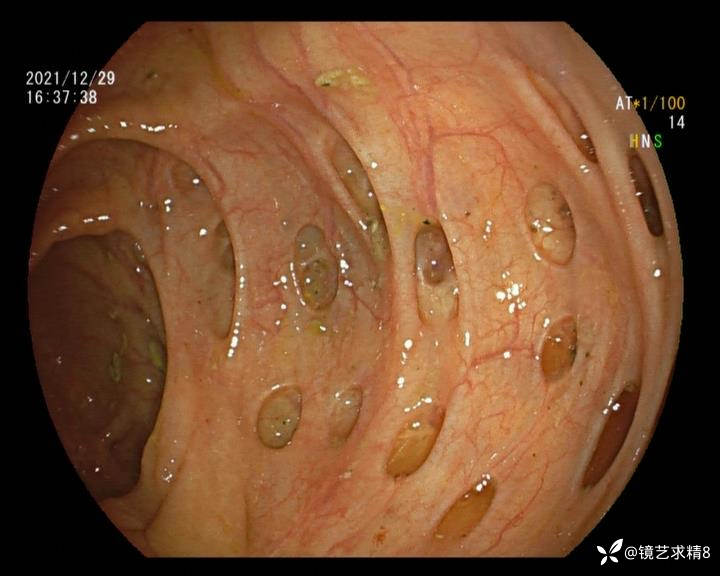

结肠内违建⥤结肠多发憩室☞续

患者以消化道出血入院,胃镜未见异常,肠镜进入乙状结肠就看到很多憩室,同时还看到肠腔用清肠药后移动下来1枚尖锐的枣核,这么多憩室,这个枣核扎入憩室的机会非常大,推测应该是掉入一坑🕳就算出来还会有很多坑🕳🕳🕳等着,掉入憩室内很容易刺破血管,这可能就是消化道出血的原因,继续前进可以看到有一些憩室内翻,还有一些息肉,问题来了,那么多憩室,犯罪分子是抓住了,它在那些憩室内作过案?到达回盲部后挨个冲洗,但憩室大小又不足以把镜头进入憩室内观察,针对有血块的憩室冲洗后可疑出血的以夹子闭合或套扎,取出枣核,如果有锥形透明帽可能钻入憩室精准电凝效果更好,若内镜下操作失败介入治疗成功率更高,经内镜下治疗后观察未再出血出院。

亚洲人群结肠憩室主要发生在右半结肠,然后随着年龄的增长而延伸到左半结肠和双侧结肠。相比之下,欧美人群80%的结肠憩室好发于左半结肠,其中乙状结肠憩室占 70%,而大多是假性憩室。 然而,与憩室炎主要发生在左半结肠不同,东西方人群的憩室出血均主要发生在右半结肠,可能与右半结肠的憩室更宽大及憩室血管更易受到损伤相关。